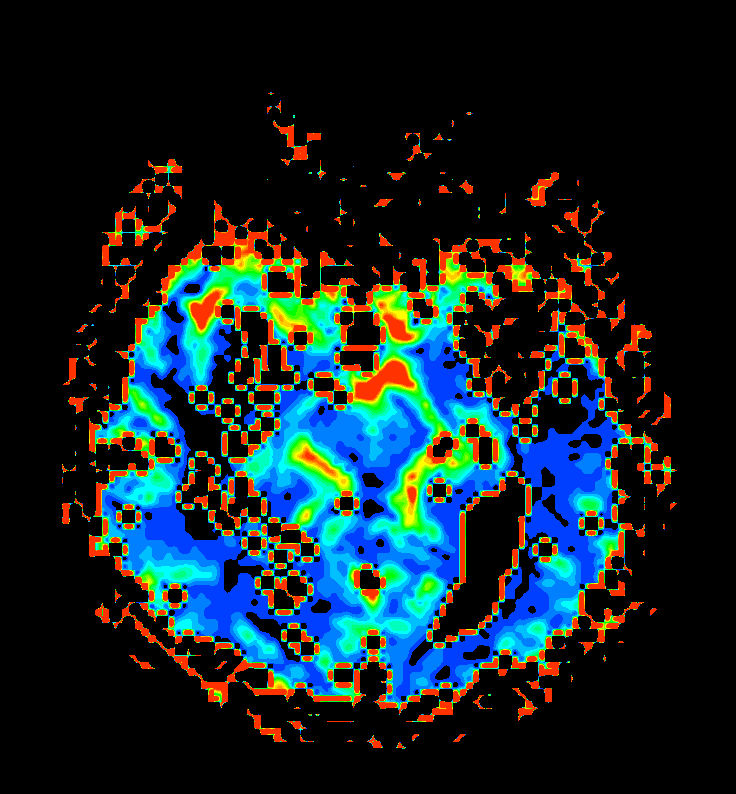

Patient with a large brain lesion. AI based SmartSpeed is utlized to shorten scan time without compromise in image quality. Advanced imaging techniques like pCASL and 3D APT are used to perform contrast-free brain imaging to assess perfusion and tumoral activity. SWIp 3D susceptibility weighted offers the high sensitivity required to visualize deoxygenated (venous) blood or calcium deposits. A single synthetic (SyntAc) brain quantification scan is added. The resulting data of this scan can be used as input for advanced third party processing software* to synthesize MR images with different contrasts, brain parenchyma fraction maps and/or brain segmentation maps.

Axial T2* Perfusion (60 dynamics)

Axial T2* Perfusion (TTP)